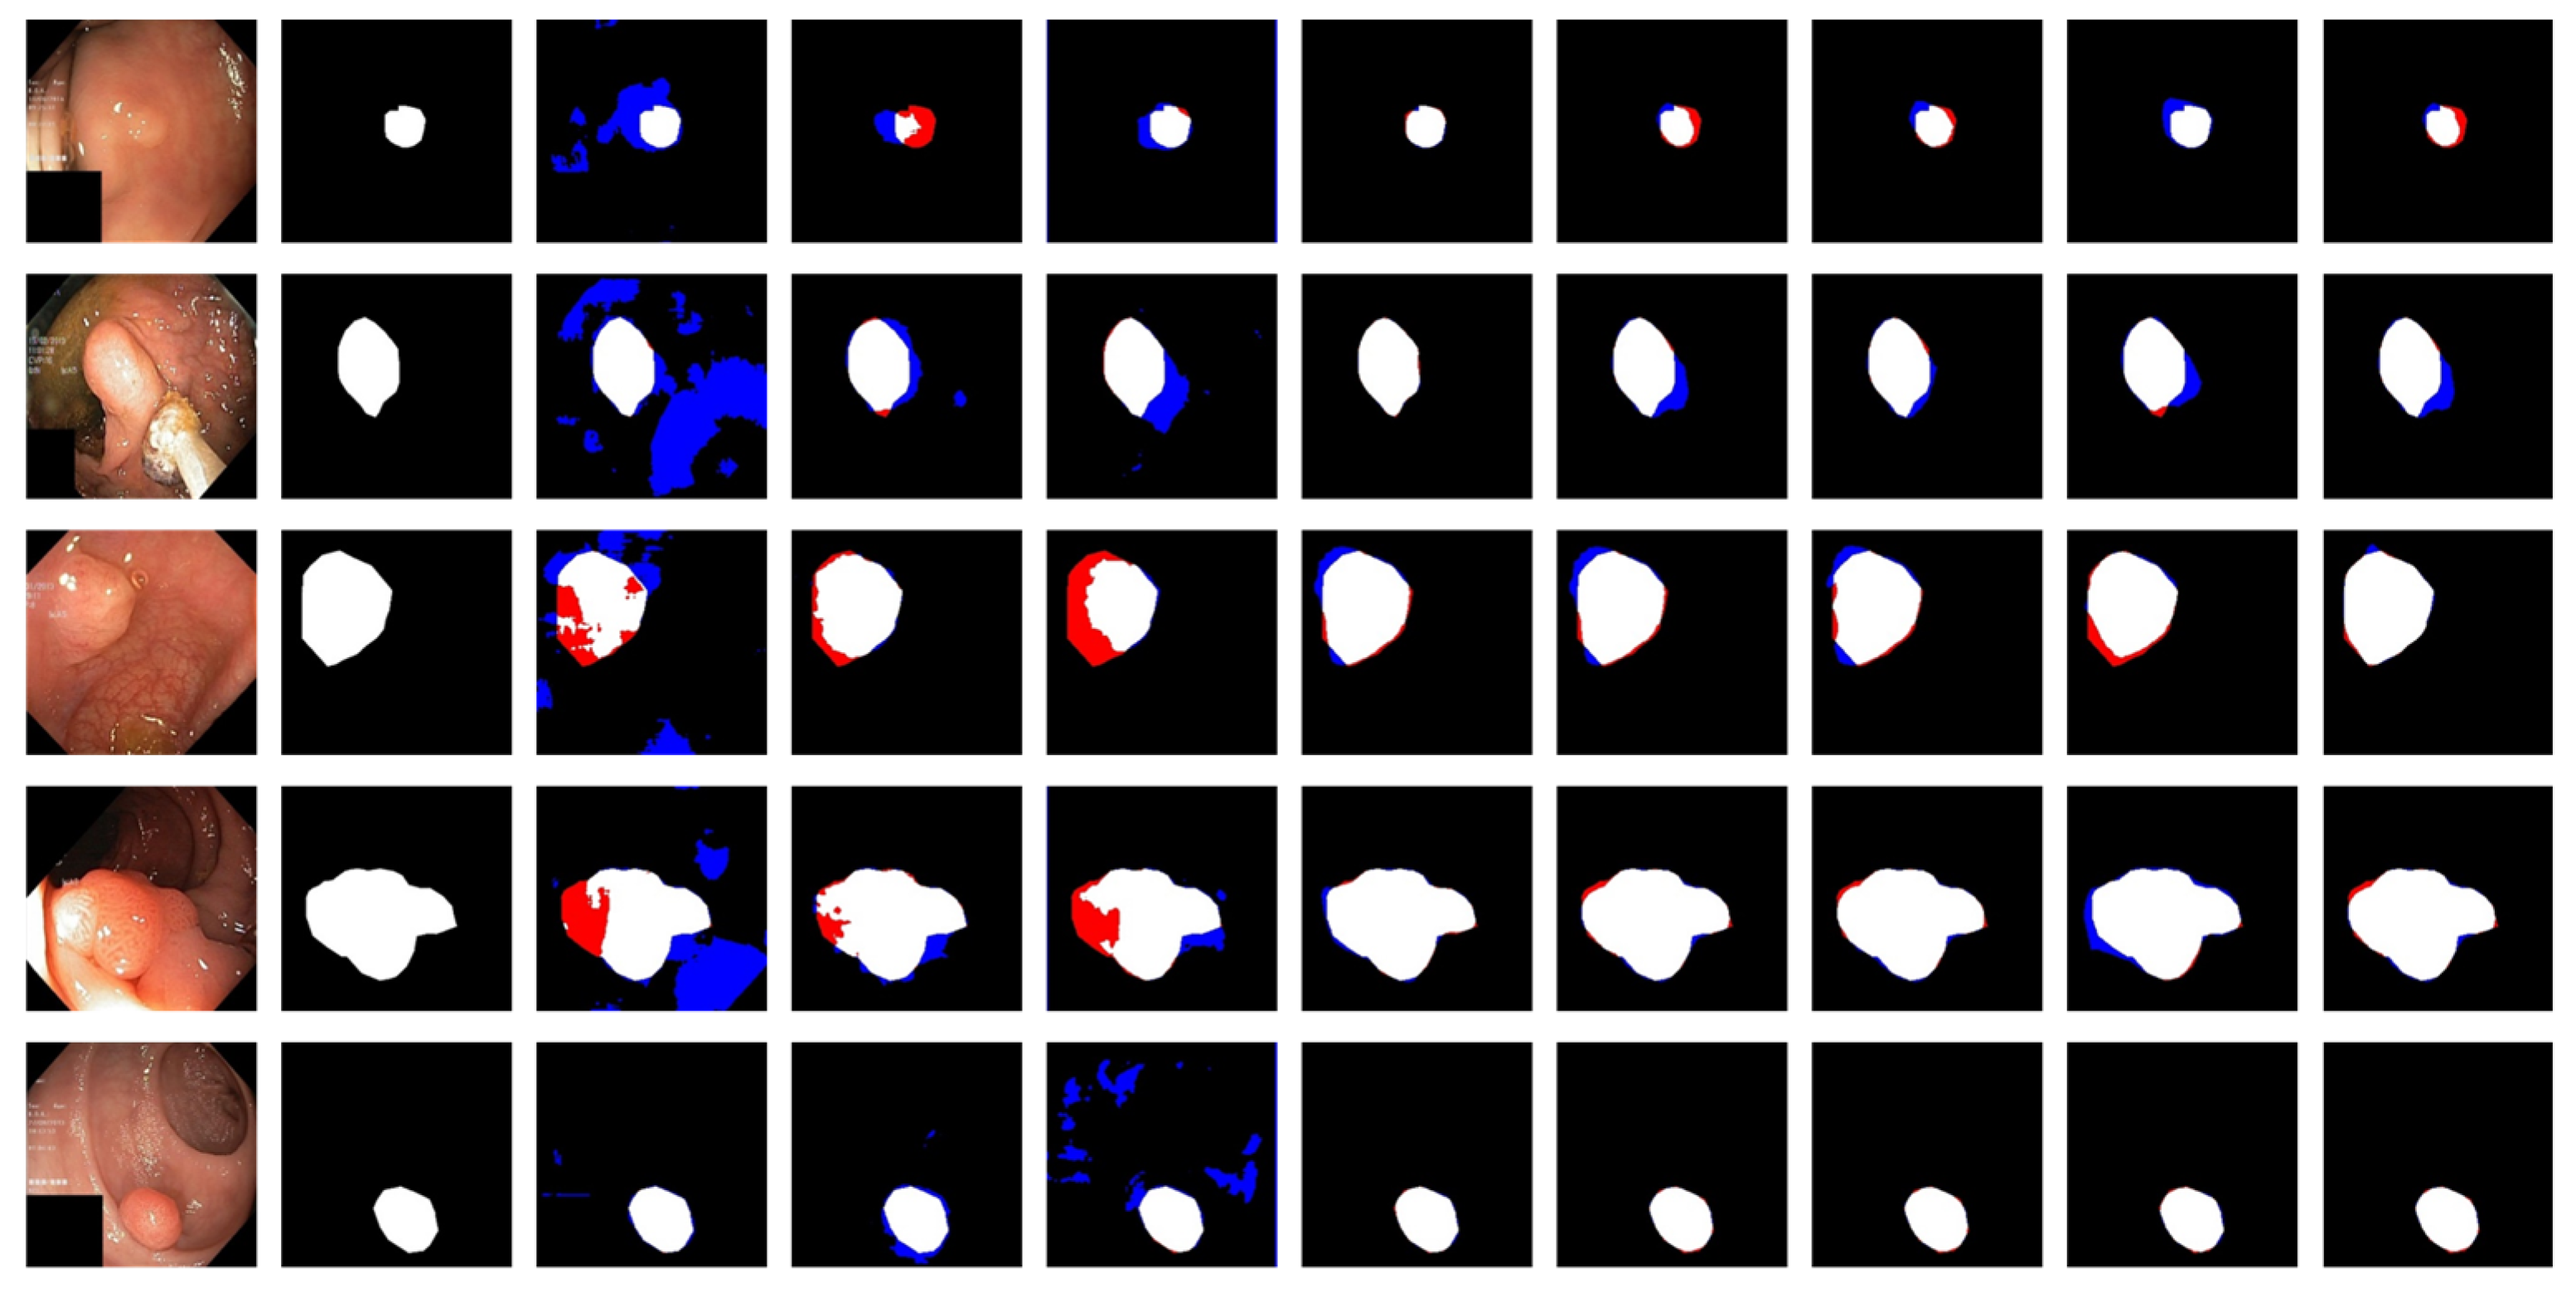

3.4. Experimental Results